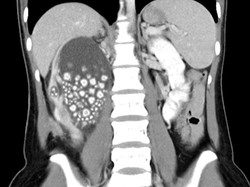

Batu ginjal adalah endapan mineral di ginjal akibat pola makan tidak sehat dan berat badan berlebih. Pelajari penyebab dan cara pencegahannya.